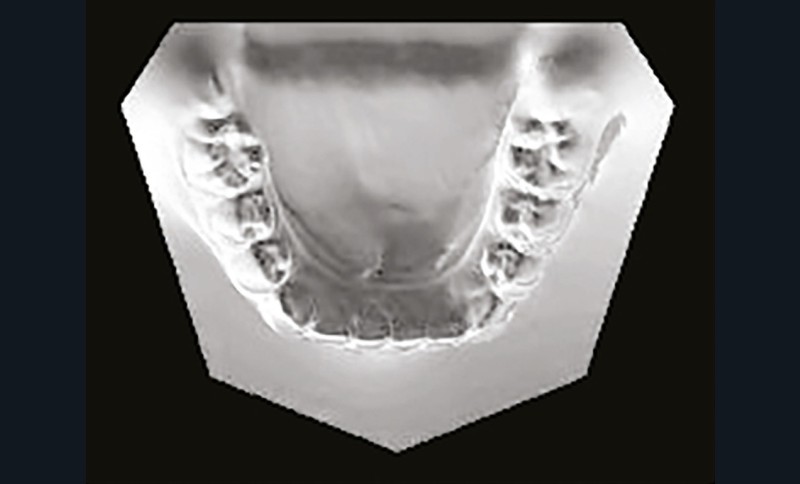

Son profil convexe s’inscrit dans un contexte de classe II squelettique par rétrognathie mandibulaire normodivergente sur un schéma de Classe II/2 avec supraclusion et encombrement modéré (fig. 1 à 7).

La formule dentaire est complète, avec un léger retard d’évolution des deuxièmes molaires (fig. 8).